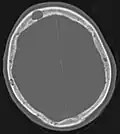

-

Axiale Computertomografie einer osteoplastischen Metastase im Schädelknochen eines Patienten mit Prostatakarzinom. Deutlich ist die Ausdehnung der Metastase über die ursprünglichen Knochengrenzen hinaus zu erkennen. -

Im Vergleich dazu eine Computertomografie osteolytischer Metastasen in den Schädelknochen einer Patientin mit Mammakarzinom. Zu sehen ist eine größere Osteolyse frontal und mehrere kleinere. -